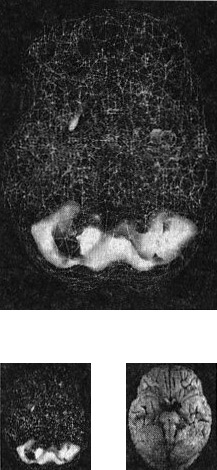

В этой книге используют трехмерные снимки мозга двух видов. Первый — это трехмерные снимки поверхности, которые фиксируют верхние 45 % активности мозга. На них показано кровообращение в коре мозга и подкорковых областях. По этим снимкам мы определяем области нормального кровообращения и области со сниженным доступом крови. С помощью таких томограмм выявляют инсульты, травмы и ущерб от наркотиков. Снимок здорового мозга должен показать ровную симметричную активность по всей поверхности коры мозга (рис. 2.1 и 2.2).

Трехмерное изображение поверхности здорового мозга ОЭКТ (вид поверхности сверху и снизу)

Рис. 2.1 Вид сверху

Полная симметричная активность

Рис. 2.2 Вид снизу

Сниженная активность выглядит на подобных сканах как дыра или вмятина. Эти «дыры» и «провалы» не означают, что активность мозга в этих местах совсем на нуле, она просто снижена, так как компьютер настроен показывать только верхние 45 % активности. Все, что меньше этого значения, выглядит как дыра или вмятина. Порог в 45 % выбран, поскольку он соответствует двум стандартным отклонениям от нормы[1] и, согласно нашим данным и данным других исследователей, является оптимальным для диагностических целей.

Второй тип томограмм — это трехмерные функциональные снимки, в которых компьютер сначала вычисляет среднюю активность мозга, а затем показывает верхние 15 % активности. Они помогают увидеть гиперактивные области, что полезно в диагностике припадков, разных типов тревожности и депрессии.

Здоровый трехмерный функциональный снимок (рис. 2.3 и 2.4) должен показывать активность (белым цветом) в задней части мозга (мозжечке) и визуальной, или затылочной, коре и среднюю активность в остальных местах (показано сеткой).

Трехмерное изображение функциональной активности здорового мозга ОЭКТ (вид поверхности сверху и снизу)

Рис. 2.3 Вид сверху

Мозг. От хорошего к превосходному

Рис. 2.4 Вид сверху

Примечание: В тексте книги будут использоваться иконки, которые помогут читателю понимать сканограммы и увидеть их отличия от нормы. Рис. А состоит из двух иконок: трехмерного изображения поверхности здорового мозга, вид сверху; и модели мозга с той же самой перспективы.

Рис. Б показывает трехмерный снимок поверхности здорового мозга, вид снизу, а нижняя иконка — это модель мозга с той же перспективы.

Рис. В показывает трехмерную картину активности здорового мозга, вид сверху, а ниже показан мозг в этой проекции.